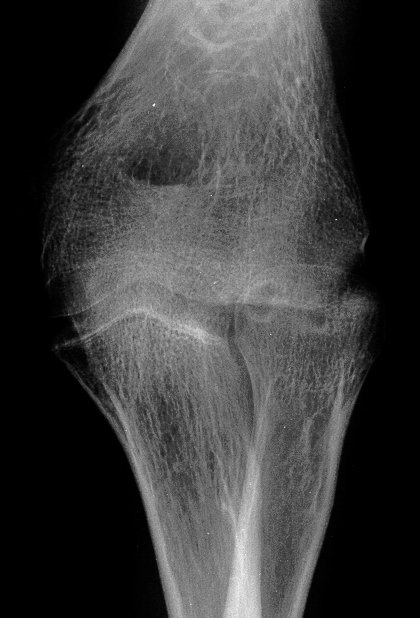

Five years later, he has limited motion (E/F 35/100) and painful clicking with elbow flexion and extension.

Plain films show humeral osteophytes and posttraumatic changes of the capitellum and radial head.

Treatment options? Do nothing, Open reduction and bone graft, sequestrum excision or radial head excision. In this case, at surgery, the loose articular fragment was too thin to allow reliable fixation, and was simply excised.

Postoperatively, pain is improved, although some clicking persists. Range of motion is marginally improved. Radial head excision remains an option if he has painful problems later.